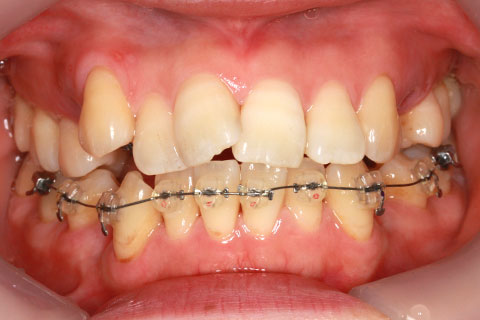

治療前

治療中

治療後

- 年齢・性別

- 23歳女性

- 治療期間

- 1年6ヶ月

- 抜歯

- 上顎4番

- 治療費

- 110万円(税込み)

- 備考

- ハーフリンガル矯正

- 治療内容

- 上下前歯部凸凹の改善

- 施術の副作用(リスク)

- 裏側矯正の特性上、表側矯正と比較すると治療期間が長くかかる場合が多い。